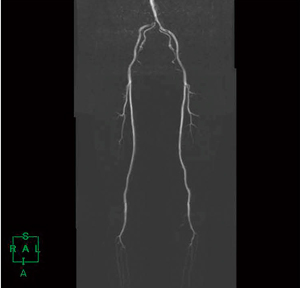

図5 非造影下肢MRA全長つなぎ合わせ画像

下肢領域の非造影MR angiographyにおける撮像法のひとつに,心周期2時相の差分により動脈のみを選択的に描出させるsubtraction angiographyがあり,当院使用のMRI装置においては非造影下肢MR angiographyアプリケーション“3D Delta Flow”が使用可能である。3D Delta Flowは,高速スピンエコー法ベースのシーケンスであり,心拡張期と心収縮期の撮像を行い,オートサブトラクションが行われ下肢動脈のみ描出するアプリケーションである。下肢動脈全長を3分割にて撮像を行うため,撮像後に画像のつなぎ合わせ作業を行う必要があるが,操作方法が簡便なFusion機能により5〜10分程度で作成可能である(図5)。